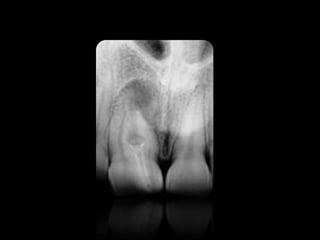

CARIES